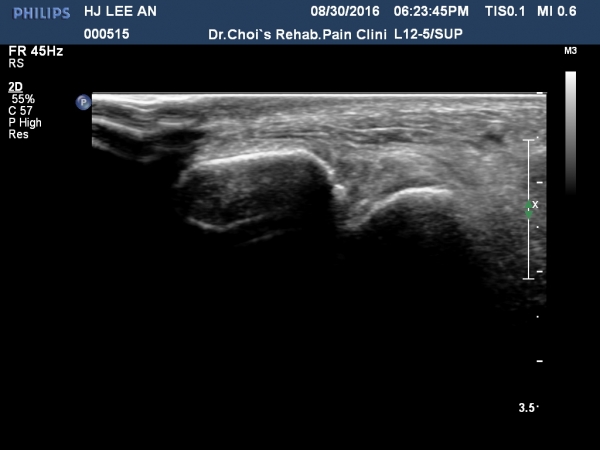

¹ß¸ñ ¾ÕÂÊ Á¾´Ü¸é°Ë»ç¿¡¼­ °üÀý³» ¼ö¾×Àú·ù´Â ¶Ñ·ÈÇÏÁö ¾ÊÀ¸³ª °æ°ñ °Å°ñ Á¢Ã˺ο¡ ¼Ò·®ÀÇ

¼ö¾×Àú·ù°¡ °üÂûµÊ(»çÁø 1, 2).